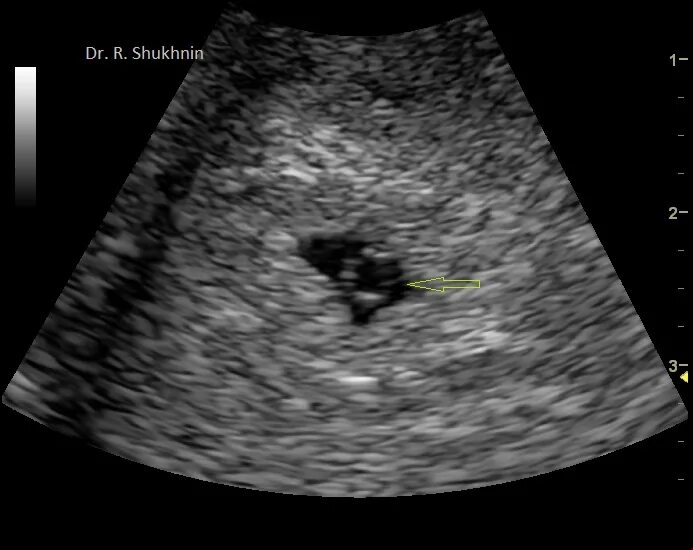

Желточный мешок увеличен